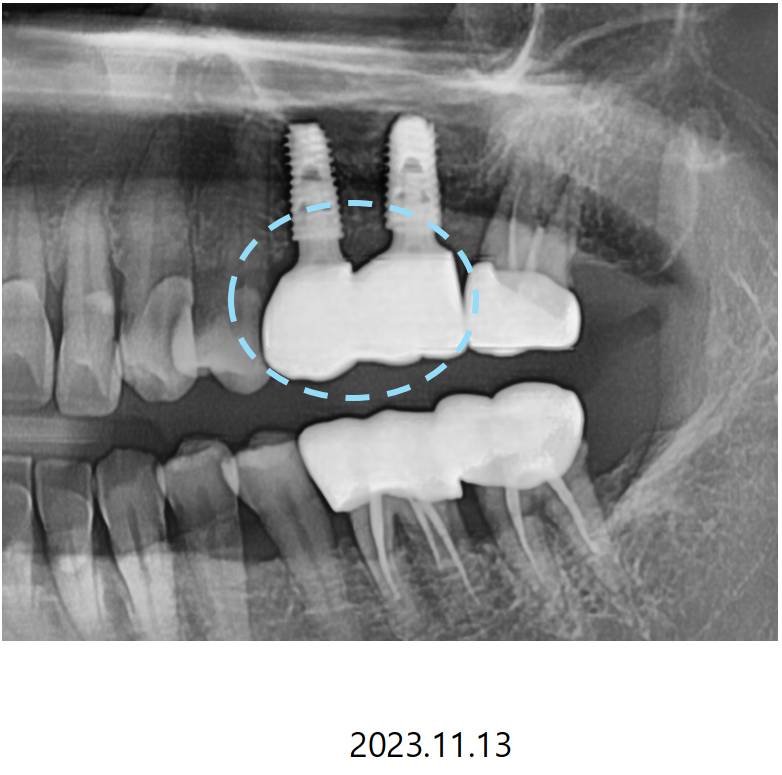

CT를 분석하여 미리 계획해둔 자리에

가이드를 장착하고 심은 덕분에

해당자리 상악동 손상없이 안전하게

상악동 거상술과 임플란트 식립을 마쳤습니다.

이번에 진행한 상악동 거상술은

상악동 수직 거상술로 수압을 이용해 막을 들어올려서

안쪽에 뼈를 채우고 해당자리에

계획한 굵기와 길이의 픽스처를 심을 수 있게 하는 방법입니다.

임플란트의 경우

자연치보다 뿌리가 작고 머리가 큰 가분수 형태라서

힘을 잘 견디고 음식을 덜 끼게 하기 위해서

맞춤형 지대주(맞춤 기둥)와 더불어 두개의 크라운을 붙여

스플린트 형태로 만들어드

리고 있는데요,

덕분에 식사하는 힘을 더 잘 받을 수 있어서

임플란트가 찢어지거나

보철이 깨지는 등의 문제를 줄일 수 있게 되었습니다.